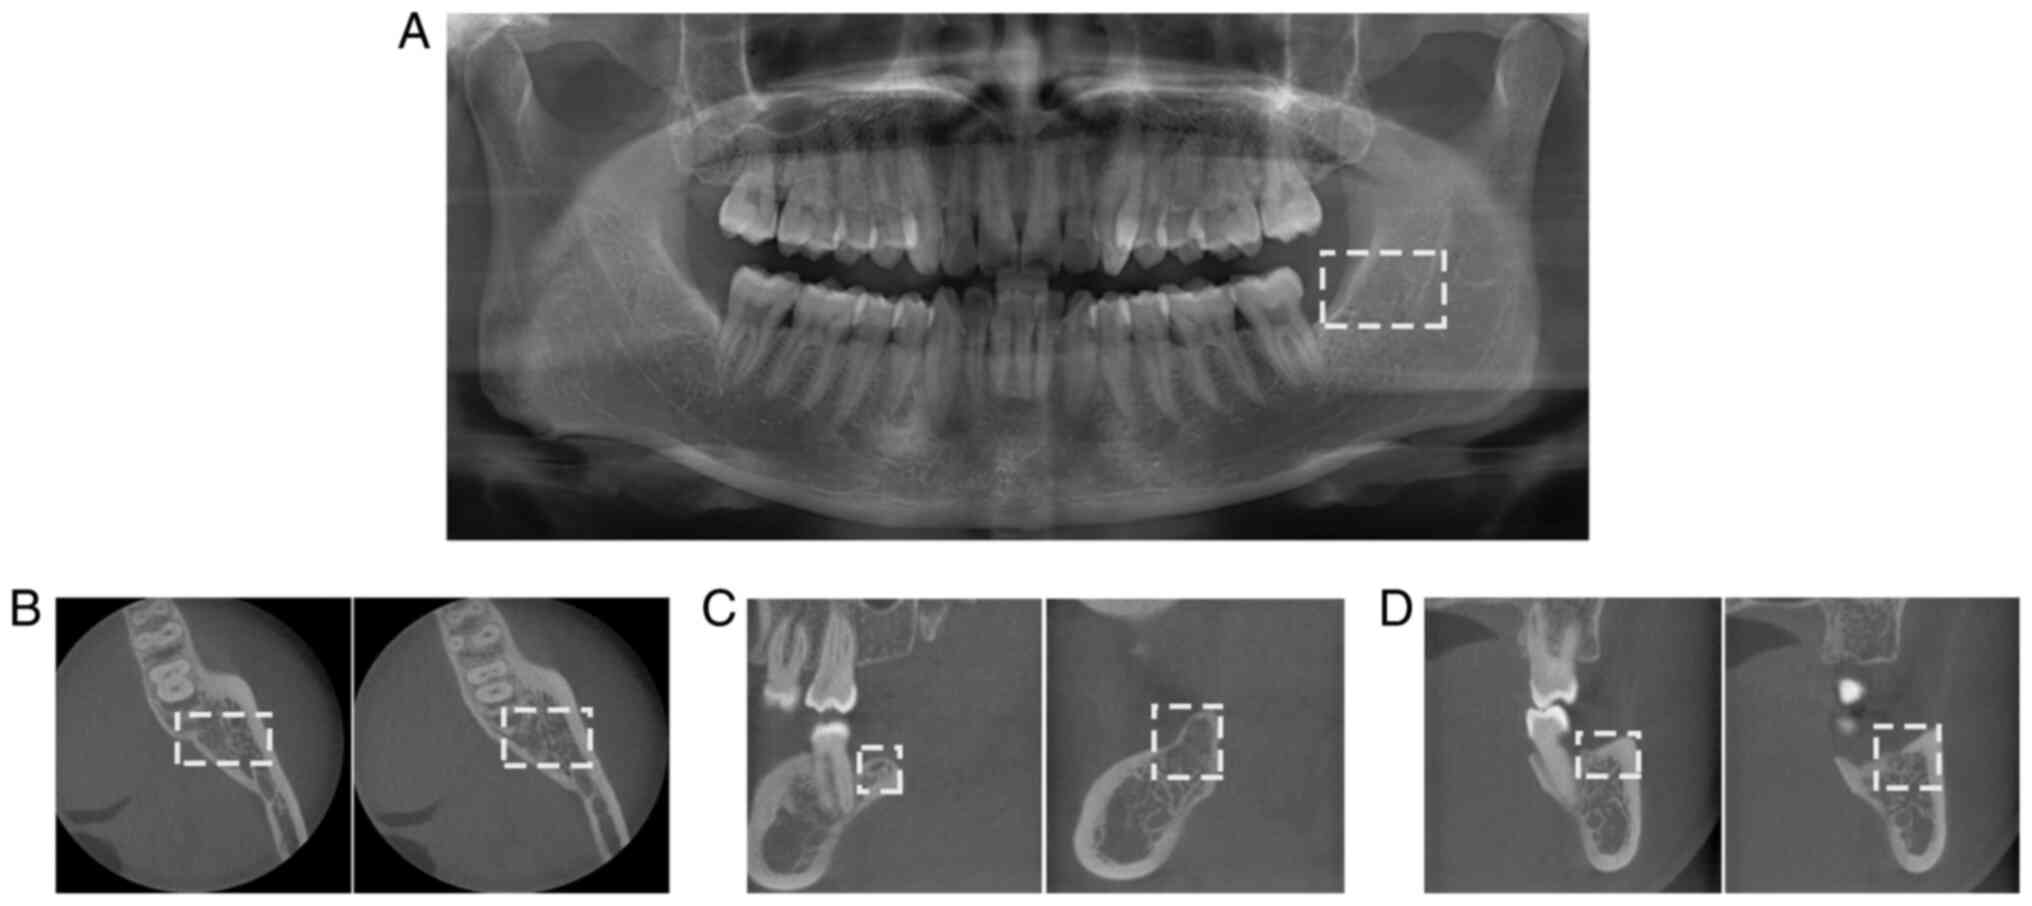

Persistent trismus following mandibular third molar extraction and its management: A case report and literature review

Trismus is one of the common complications which occur following the extraction of mandibular impacted third molars. This generally occurs due to low‑grade infection, repeated muscle stimulation, as well as other causes. This symptom is usually relieved after 1 to 2 weeks; however, it may persist for >1 month post‑operatively in very rare cases. The present study reports the case of a patient with trismus at 45 days following mandibular third molar extraction. The patient received local and systemic anti‑inflammatory treatment, combined with incision and drainage therapy under local anesthesia. In the present study, an analysis of the factors associated with the occurrence and development of trismus is also included, as well as appropriate management strategies in order to provide an effective treatment method for affected patients and for the prevention of trismus in the future.

Figure 1

Figure 2

Figure 3

Figure 4

Figure 5